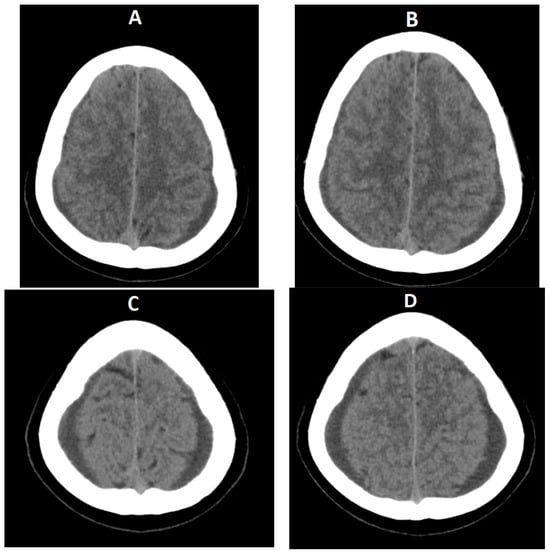

- Subdural fluid collections—mostly bilateral hygromas—are described in 43–50% of patients [5,19]. Hygromas occur because of the enlargement of the subdural space secondary to the loss of the CSF, while subdural hematomas may be caused by tearing of the abnormally engorged and dilated cortical veins [32]. Drainage of these collections will not resolve them successfully if the CSF leak is not identified and treated [36].

- Signs of brain sagging include flattening of the ventral pons, effacement of the prepontine and perichiasmatic cisterns, or downward displacement of the cerebellar tonsils and brain stem [5,8], which may mimic Chiari type 1 malformation. However, in SIH, the tonsils maintain normal shape and do not descend more than 5 mm below the foramen magnum [37]. Moreover, the findings associated with syringomyelia would argue for the diagnosis of Chiari type 1 malformation [32].

- Dural venous sinus engorgement appears usually as a dilation of the transverse sinuses, which is subtle and often diagnosed retrospectively, by comparison of pre- and post-treatment images [5].